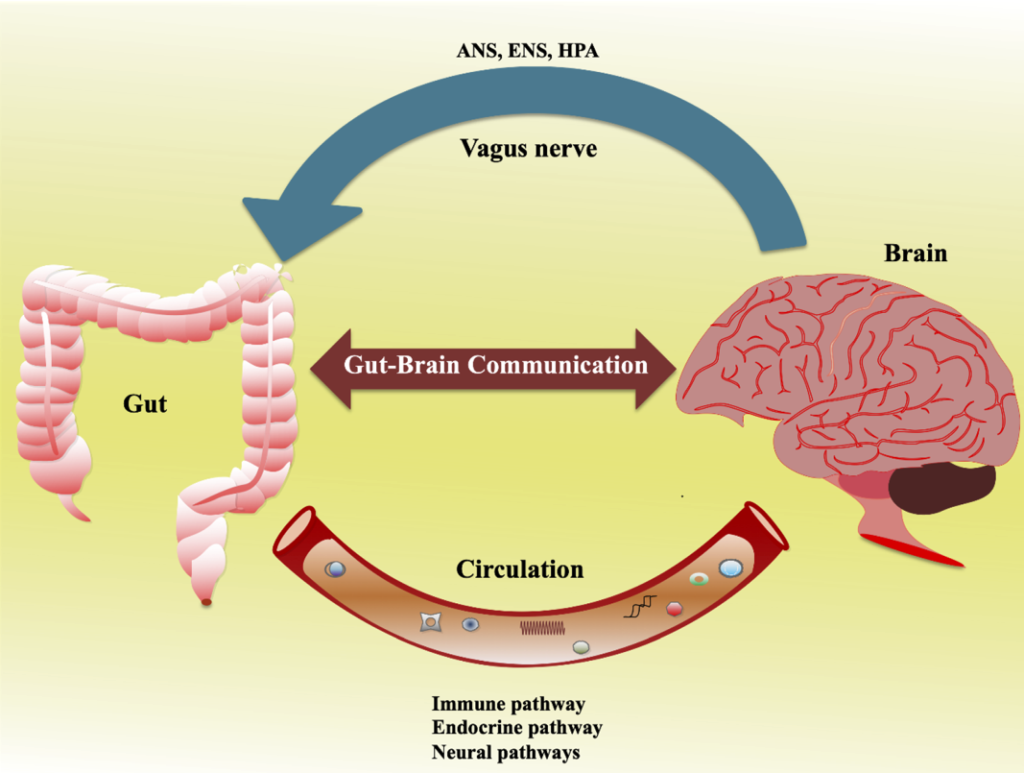

Your Gut Is Talking to Your Brain Constantly

You have probably heard the phrase “gut feeling.” Turns out, that is barely metaphorical. If you have ever “gone with your gut” to make a decision or felt “butterflies in your stomach” when nervous, you are likely getting signals from an unexpected source: your second brain. Hidden in the walls of the digestive system, this “brain in your gut” is revolutionizing medicine’s understanding of the links between digestion, mood, health and even the way you think. Scientists call this little brain the enteric nervous system.

Through direct signals from the vagus nerve, which connects the brain and the gut, as well as through molecules secreted into the bloodstream from gut microbes and immune cells that traffic from the gut to the rest of the body, the brain and the digestive tract are in constant communication. What is genuinely shocking is the scale of the influence flowing upward – from gut to brain. Recent studies have underscored the role of the gut microbiome in conditions such as Parkinson’s disease, with evidence indicating that gut dysfunction and pathological features can precede motor symptoms by decades. Your belly may be warning your brain about disease long before your doctor can detect it.